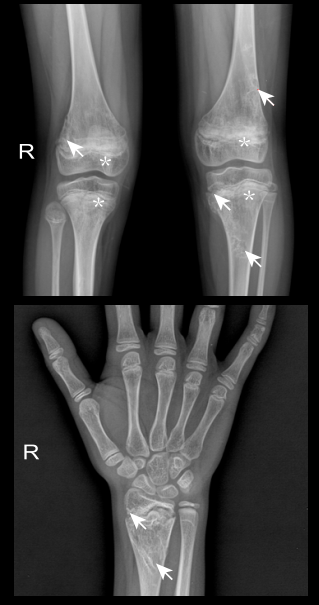

患者的病灶部位的放射学检查结果,包括股骨远端和胫骨近端硬化边缘的溶骨性病变,伴有轻度骨膜反应(箭头),股骨远端和胫近端干骺端病变(星号)(上图)和桡骨远端硬化边缘的溶解性病变(箭头)(下图),引自 Wang et al., 2023, Immunity 56, 1485–1501